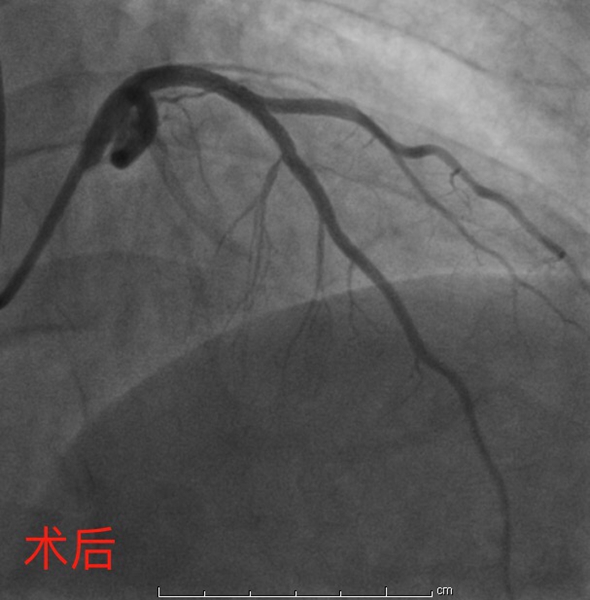

4月27日,彭道地主任与范爱德副主任医师为其手术。术中,冠脉造影提示:冠状动脉多支多处狭窄病变,其中左前降支近中段弥漫狭窄50-95%,第一对角支粗大,开口至近端狭窄75%-85%。“分叉狭窄病变”手术风险大、操作较复杂。但两位经验丰富的专家还是顺利将2枚支架植入狭窄血管,血管打通,病人病情得到明显缓解。